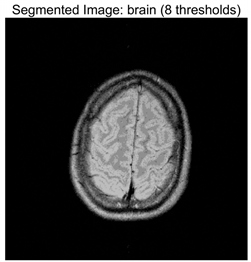

Table 8 presents the distributions of the optimal thresholds selected by each algorithm on the image histograms. Table 9 reports the mean and standard deviation of the best fitness values obtained by each algorithm based on the Otsu objective function, along with their average performance rankings. Furthermore, Table 10, Table 11 and Table 12 summarize the mean, standard deviation, and average ranking of each algorithm in terms of PSNR, FSIM, and SSIM, respectively. The experiments cover four threshold levels (4, 6, 8, and 10), with all results obtained through optimal threshold search using the Otsu criterion.

Table 9 focuses on the optimal fitness values obtained based on the Otsu objective function (maximization of inter-class variance), which directly reflects the algorithms’ ability to search for segmentation thresholds. Higher Ave values indicate that the thresholds are closer to the global optimum, while lower Std values reflect greater consistency across multiple runs. From the data distribution, RLTC-SCA exhibits a dual advantage of “high Ave + low Std” across all image and threshold-level combinations. For instance, in the brain image (a medical brain image with complex grayscale distribution), when TH = 4, RLTC-SCA achieves an Ave value of 3.7306 × 103, comparable to AGPSO and MVO, but its Std value (2.3126 × 10−12) is only 1.53 × 10−11 times that of AGWO (1.5156 × 10−1), showing virtually no fluctuation. At TH = 10, its Ave value (3.7694 × 103) still surpasses standard SCA (3.7644 × 103) and AGWO (3.7691 × 103), with a Std value (1.3312 × 10−1) amounting to merely 3.81% of IVYA (3.4907 × 100), demonstrating stable threshold-search accuracy even at high threshold levels. In the camera image (industrial scene image with low grayscale contrast), at TH = 4, RLTC-SCA’s Ave value (4.6008 × 103) is 0.01% higher than the second-best AGPSO (4.6003 × 103), while its Std value (0.69397) is only 39.44% of standard SCA (1.7594), validating that the reinforcement learning-based action selection strategy can dynamically adjust search actions to avoid threshold selection bias in smooth grayscale distributions. In contrast, algorithms such as IVYA, lacking guided global exploration, show lower Ave values and Std values exceeding 3.0 × 100 in most images, ranking last (8th) in the Friedman ranking, compared with RLTC-SCA ranked 1st.